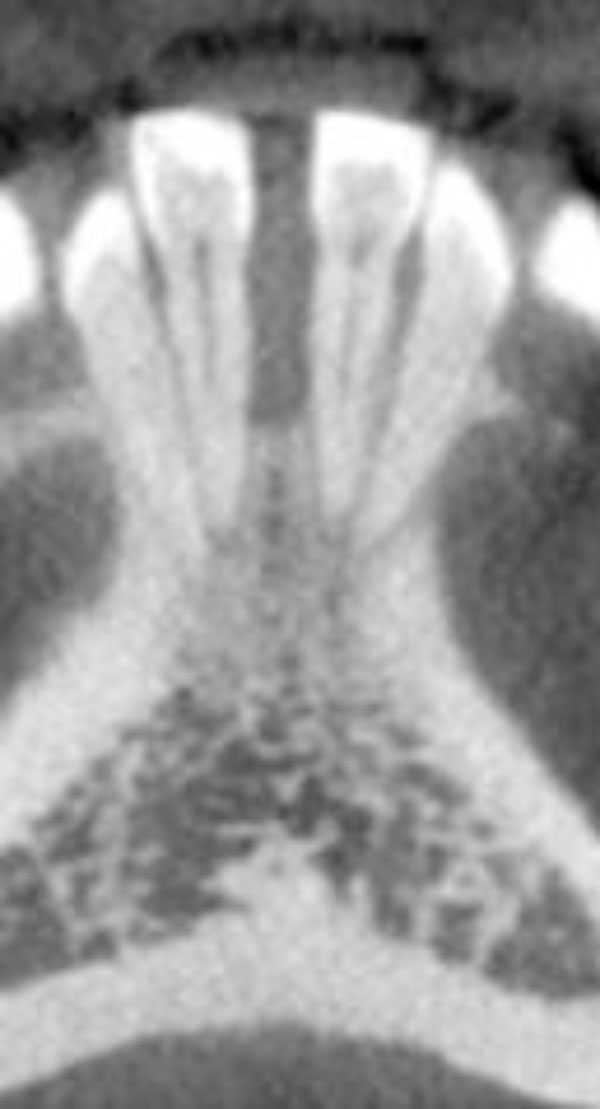

Clinical examination revealed the space formation between teeth 24 and 25 (Fig. 1a). The overlying mucosa and gingiva appeared normal in color. Deep probing elicited bleeding from the problem site. Radiographic evaluation revealed a well-circumscribed, low-density, radiolucent lesion between the mandibular central incisors, with spacing between teeth 24 and 25 (Fig. 1b) as well as thinning and expansion of the buccal and lingual cortical plates (Figs. 1c-1e). No other pathology was detected by the oral and maxillofacial radiologist on the images.

Expansion of the lingual aspect in the anterior mandible.

Three-dimensional image showing the loss of vertical dimension and buccolingual expansion of the alveolar bone.